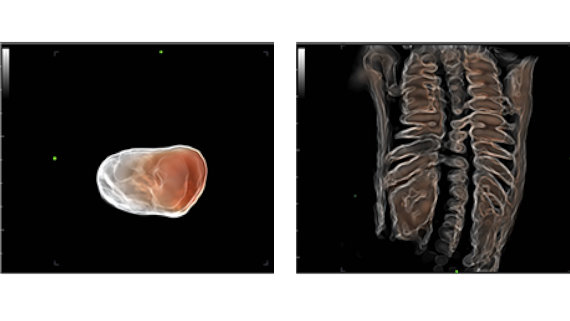

Smart Face, tek dokunu?la fetal yΟΦz i?in h?zl? ve ak?ll? optimizasyon sa?lar. Hacim verilerinde, kordon, plasenta, rahim ve ekstremiteler gibi oklΟΦzyonlar? an?nda kald?r?r ve istenmeyen gΟΦrΟΦltΟΦ bilgilerini ortadan kald?r?r, b?ylelikle nihayetinde, daha sade bir ?ekilde fetal yΟΦzΟΦn optimum g?rΟΦnΟΦmΟΦnΟΦ olu?turur.

- Otomatik g?rΟΦntΟΦ optimizasyonu ile basitlik --- Smart Face

- Smart Face, tek dokunu?la fetal yΟΦz i?in h?zl? ve ak?ll? optimizasyon sa?lar. Hacim verilerinde, kordon, plasenta, rahim ve ekstremiteler gibi oklΟΦzyonlar? an?nda kald?r?r ve istenmeyen gΟΦrΟΦltΟΦ bilgilerini ortadan kald?r?r, b?ylelikle nihayetinde, daha sade bir ?ekilde fetal yΟΦzΟΦn optimum g?rΟΦnΟΦmΟΦnΟΦ olu?turur.